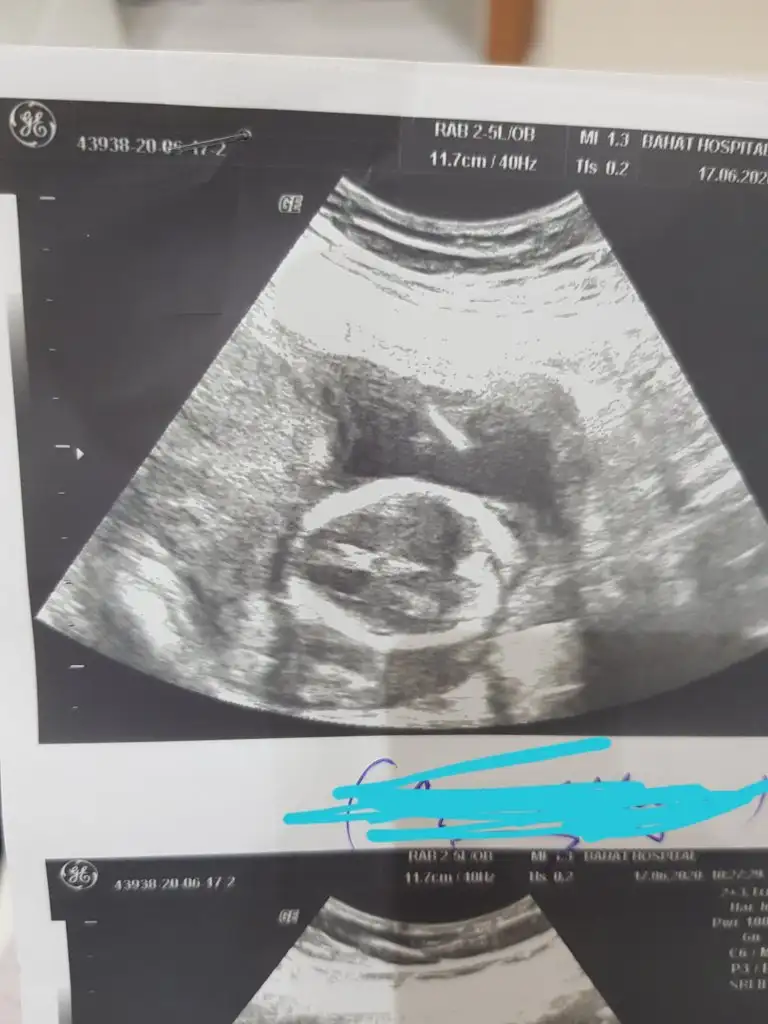

Bunlar net değilBi de bu resimler var.

ÖgrendinizmiEvet net bulamadım en net resmi bu doktor net çekmemiş aslında 12 haftalık teşekkür ederim

Kaç haftalık usg sanki erkek gibi eminde olmadım 11 12 13 haft usgler olmalı tekrar usg paylaşınMerhabalar tahmininizi çok merak ediyorum :)

Üçlü taramada büyük ihtimalle kız olduğu söylendiNet degil usg tek tek çekermisiniz usgler yada başka usg olursa paylaşın 12-13 haftalarda olabilir şimdilik eminde değilim kız gibi gibi emin değilim tekrar usg paylaşın